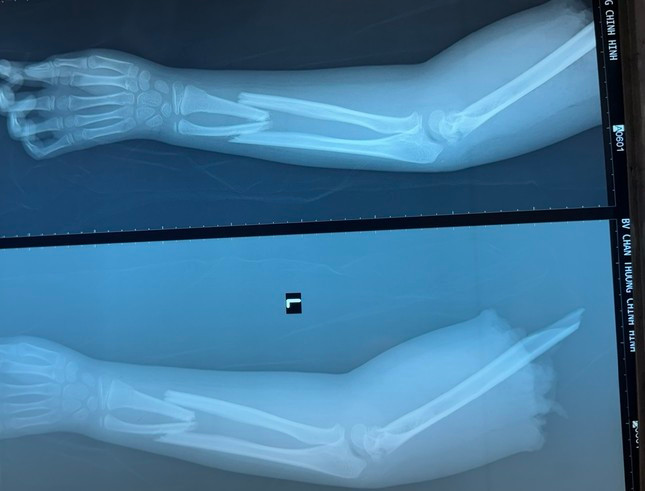

| Cánh tay của bệnh nhi bị đứt lìa thời điểm nhập viện cấp cứu |

Người nhà đã bảo quản cánh tay trong thùng đá và chuyển cùng bệnh nhi đi cấp cứu. Tại Bệnh viện Chấn thương Chỉnh hình, các bác sĩ đã kiểm tra hình ảnh và phát hiện, ngoài tình trạng bị đứt lìa, cánh tay bệnh nhi còn bị gãy ở cẳng tay, vị trí đứt lìa dập nát phức tạp.